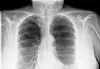

New study shows how vitamin D could help millions of people who are currently at risk of contracting tuberculosis. But more studies are needed, say scientists.

New research gives hope to millions of people from the developing world who are still at risk of contracting tuberculosis.

Something as simple as a vitamin-D supplement could perhaps offer protection from the deadly disease, which killed approximately two million people in 2015.